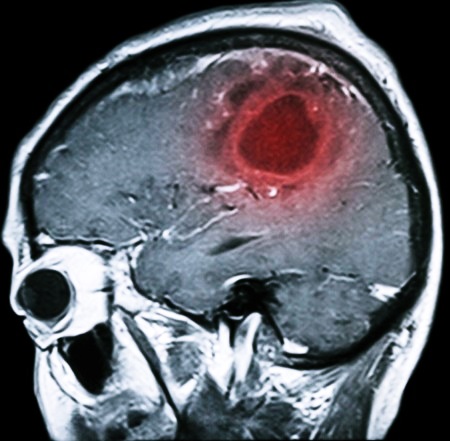

- Опухолевые процессы (рак), в частности глиобластома и киста, локализованные в различных отделах мозга, которые приводят к проблемам с оттоком ликвора или смещению структур мозга.

Для диагностики заболевания используются различные современные методы: МРТ, КТ, УЗИ и многие другие. Если форма патологии не молниеносная, то заподозрить наличие заболевания может невролог, который отметит прогресс ухудшения состояния больного, наращивание процессов нарушения сознания вместе с симптоматикой менингита.

Чтобы подтвердить диагноз, используются методы магнитно-резонансной и компьютерной томографии.